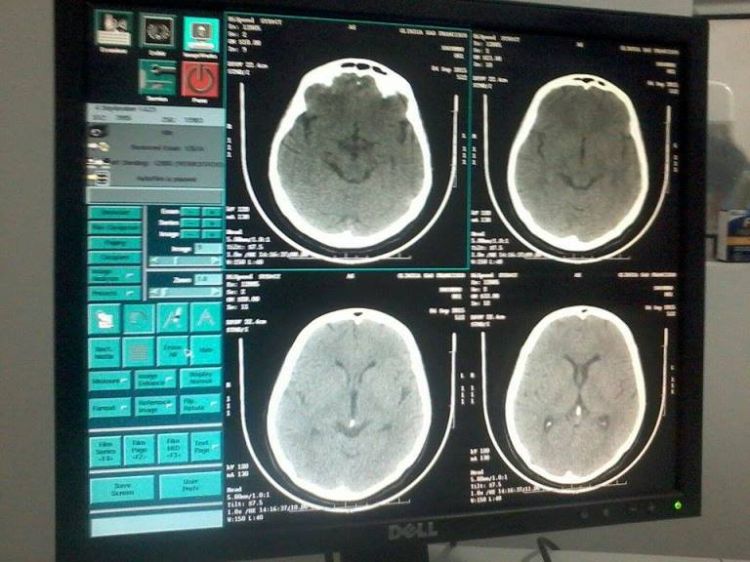

Sempre pioneira em implantação de procedimentos diagnósticos de média e alta complexidade, a Clínica São Francisco é a primeira a oferecer o serviço de tomografia computadorizada helicoidal, exame este que associa alta resolutividade à rapidez de sua realização.

Com imagens de alta definição e capacidade de cortes cada vez menores (até 1 mm) e reconstrução de imagens, a Cliníca chega a um novo patamar de evolução.